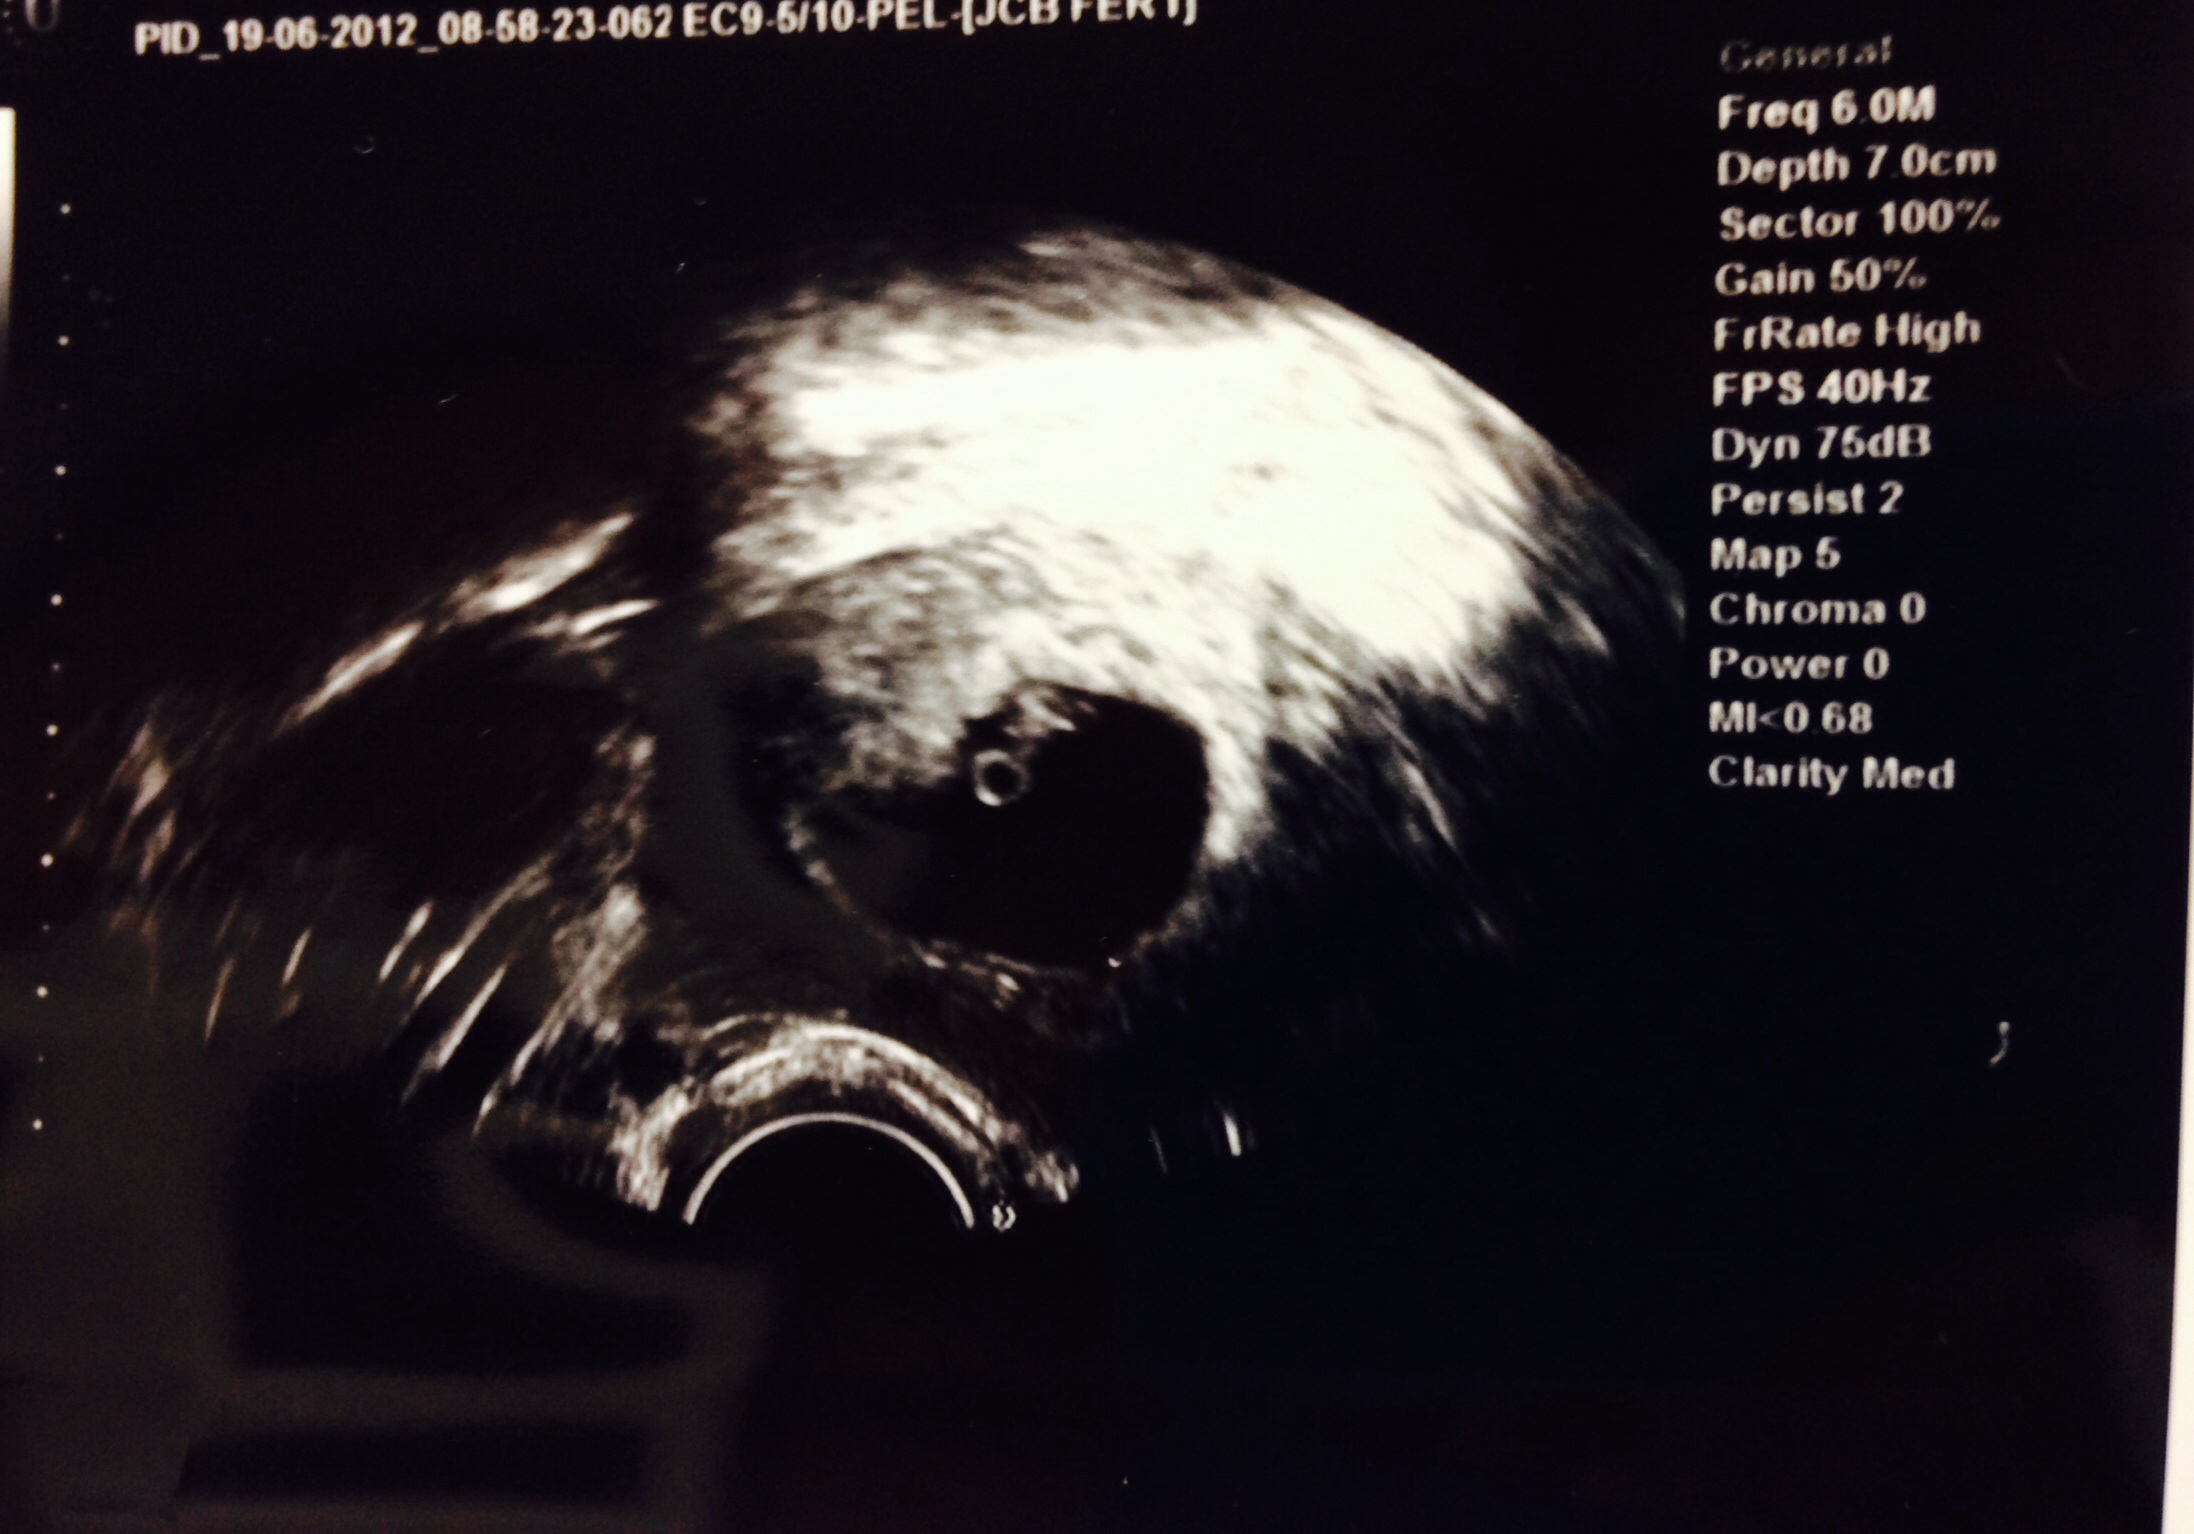

6w5d ultrasound showed one perfect baby with a beautiful heartbeat of 134bpm!

1st u/s 4/16: One beautiful hb at 144 bmp

2nd u/s 4/29: hb at 166 bmp. Graduated from RE!!